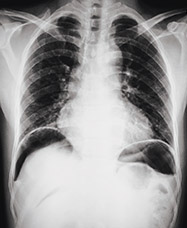

Urgent warfarin reversal in action

Connect live with a healthcare professional to explore case scenarios requiring warfarin reversal for patients with acute major bleeding or in need of urgent surgery/invasive procedures